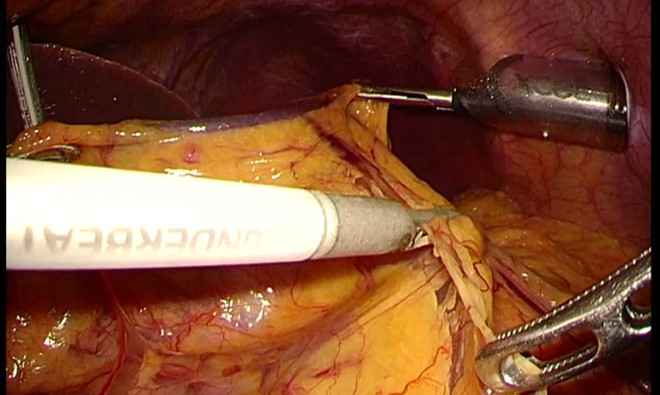

その後様々な技術革新がおこり、モニターについてはハイビジョン映像が当たり前となって、4Kや8Kも実用化に至りました。高画質3D映像での手術により、鏡視下手術の課題とされていた奥行きの認識も可能となりました。高精細の映像が得られることで、これまで認識できなかった脈管や神経、また層構造がわかるようになりました。さらに、超音波凝固切開装置を代表とする『血を出さずに切開する』『組織を焦がさずに止血する』ことを実現できる進化した道具も登場しました。胃がんをはじめ、がんの手術はリンパ節郭清といって対象臓器と周囲のリンパ節ごと切除する術式が標準です。大事な血管を温存しつつがんを取り残さない手術、がんをまき散らさずに切除する手術がこれらの技術革新によって腹腔鏡下に実現可能となったのです。

胃がん腹腔鏡手術の最大のメリットはその“繊細性”にあります。内視鏡システムを用いて近接拡大した画像を大型高精細モニターに映し出すことで、開腹手術では認識できない薄い膜や血管やリンパ管が容易に認識できます。これらを丁寧に処理することで開腹手術に比較して圧倒的に少ない出血量で手術が可能になりました。出血や浸出液を減らし輸血のリスクも下げられます。また、がん手術で特に大事な「がん細胞をまきちらさない」という点において、腹腔鏡下手術では細かく把持をすることでがんそのものを触らないで切除する手術が可能となります。

胃がん手術において、ダビンチを代表とする手術支援ロボット手術が2018年に保険収載されました。ダビンチの特徴として、没入型高画質3D映像、多関節能、手振れ防止機能、スケーリング機能(手元の動きをより小さくして術野で再現する)などがあります。

ロボットを用いることで、腹腔鏡手術の繊細さを生かして、さらに動作制限を最小限とした自由度の高い手術が可能となりました。腹腔鏡下において術者の意図が容易に再現できるようになり(術者への)ストレスがかなり軽減されたといえます。まだ、鉗子や自動縫合器などの性能は従来の腹腔鏡用に追いついたとはいえませんが、猛烈な勢いで開発が進んでいます。